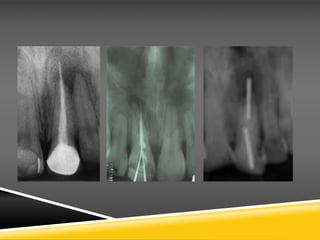

Wound Cleansing and Suturing of Flap.

After placement of the amalgam, the gauze is carefully removed fromthe bony defect

and, after copious irrigation with saline solution, a radiographic examination is

performed to determine if there is amalgam splattering

in the surrounding tissues. The flap is repositioned and interrupted sutures are

placed. Healing of the periapical area is checked every 6–12months radiographically,

until ossification of the cavity is ascertained. In order to evaluate the result, a

preoperative radiograph is necessary, which will be compared to the postoperative

radiographs later